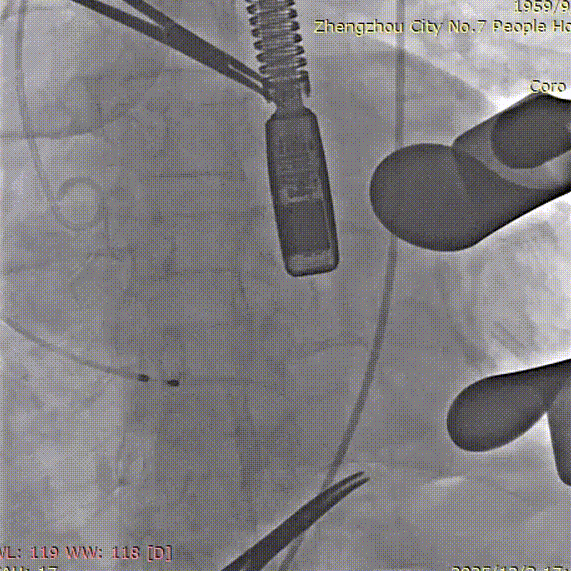

手术过程中,团队严格按照标准操作流程实施。自介入器械导入至瓣膜释放完成,器械用时约10钟。整个过程中,手术团队通过右冠窦居中造影、定位件入窦确认、释放后联合超声与造影评估,确保了瓣膜定位精准、释放平稳。术中超声评估显示无瓣周漏,血流动力学表现良好,手术过程顺利。

调整角度后造影,右窦居中位置

造影确认定位件入窦底

最后一枪造影,基本无瓣周漏